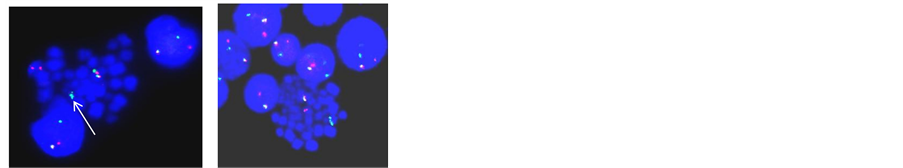

Figure 2. (a) LSI dual colour ETV6/RUNX1 ES translocation probe on metaphase and interphase cell shows ETV6/RUNX1 (Yellow signal) on der(21) with additional copy of RUNX1 and absence of ETV6 allele indicating ETV6/RUNX1 with trisomy 21 and loss of ETV6 allele; (b) LSI dual colour ETV6/RUNX1 ES translocation probe on metaphase and interphase cell shows RUNX1 amplification on der(21) (iAMP21); (c) LSI MLL/MLLT2 dual fusion probe on metaphase cell shows reciprocal MLL/MLLT2 (Yellow signal) on der(4) and der(11): t(4;11); (d) LSI TCF3/PBX1 translocation probe on metaphase and interphase cell shows TCF3/PBX1 (Yellow signal): t(1;19); (e) LSI dual colour TCF3 break apart probe on interphase and metaphase cell shows 1R1G1Y signal pattern in a specimen with no evidence of TCF3/PBX1 indicating variant t(17;19); (f) WCP 7 ( Red) and WCP 14 (Green) on metaphase cell shows t(?;7;14)(?;p12;q11.2); (g) LSI dual colour TCR-α break apart probe on metaphase cell shows residual TCR-α (Green signal) on der(11) indicating t(11;14)(p15;q11.2); (h) WCP 7 (Red) and WCP 14 (Green) on metaphase cell shows residual 7q36 region (Red signal) on 10q24 indicating t(7;10)(q34;q24); (i) LSI dual colour TCR-β break apart probe on metaphase cell shows residual TCR-β (Green signal) on 7p indicating t(7;7) (q34;q15)/inv(7)(p15q34); (j) LSI dual colour TLX1 break apart probe on metaphase and interphase cell shows green signal on der(14) indicating t(10;14)(q24;q11.2); (k) LSI dual colour TLX3 break apart probe on metaphase and interphase cell shows 1R1G1Y signal pattern indicating TLX3 translocation.

Translocation t(12;21): ETV6/RUNX1 was detected in 12.2% cases (291/2982), of which loss of ETV6 allele in 162 cases (55%) and trisomy 21 in 80 cases (27%) were the most common additional abnormalities. The ETV6 allelic loss and trisomy 21 were also detected in 5% cases (102/2101) and 37% cases (783/2101), respectively in case of ETV6/RUNX1 negative group, whereas (iAMP21) was found in 23 cases(1%) (Table 2 and Figures 2(a)-(e)).